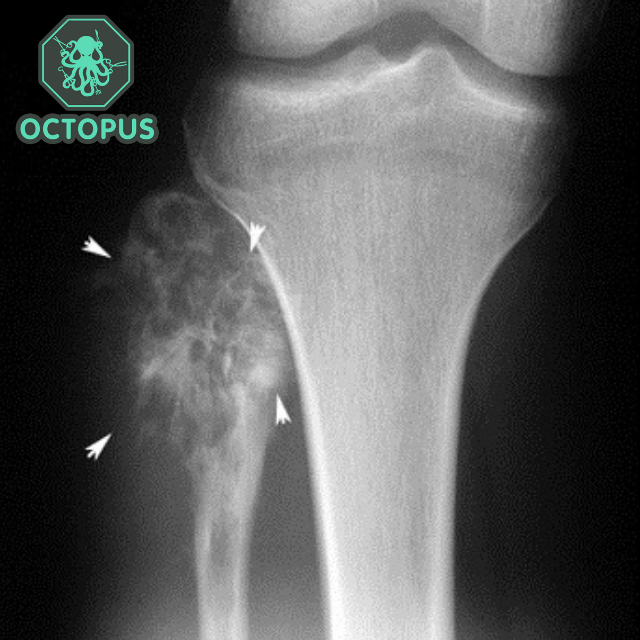

Остеосаркома коленного сустава: информация и поддержка